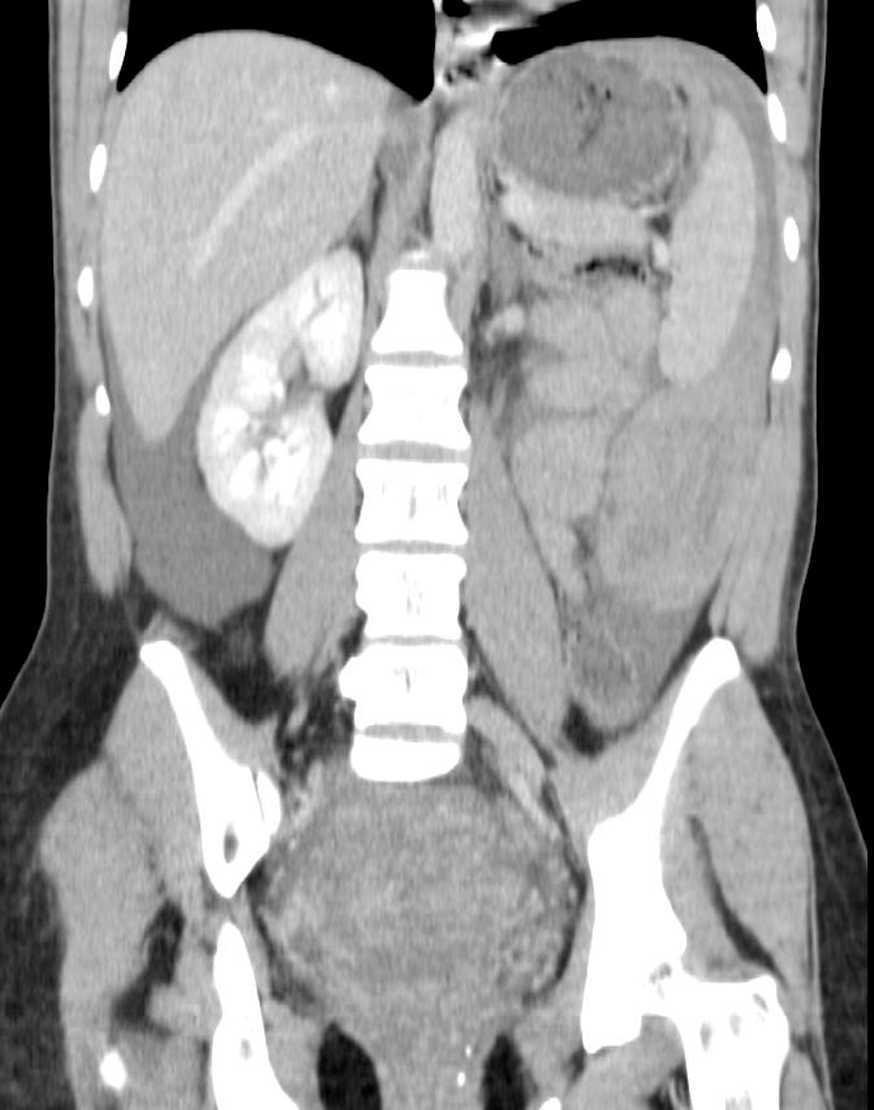

Ante la sospecha de una posible complicación abdominal se realizó interconsulta con cirugía general. Se indicó la práctica de una ecografía abdominal que constató la existencia de una colección líquida con ecos y tramas en su interior sugestiva de hemoperitoneo, con un volumen aproximado de 700 ml. Como el estado general de la paciente no requería una intervención activa urgente, se decidió realizar una TC abdominal (con y sin contraste) (figs. 3 y 4) para intentar visualizar el posible origen del sangrado. Dicha TC informó de abundante líquido libre intraabdominal diseminado, más abundante en zona parietocólica izquierda y celda esplénica, por lo que en un primer momento se contempló la posibilidad de una lesión esplénica, pero como no se pudo objetivar de una forma clara, se aconsejó valorar probable sangrado de vasos parauterinos izquierdos, dado el antecedente de un parto reciente.

Figura 3.TC. Líquido libre en cavidad abdominal.

Figura 4.TC. Colección hemática yustaexplénica.